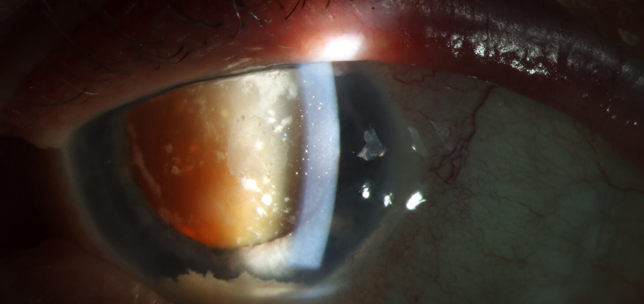

The ANTerior Segment Imaging Competition from Eye News and Keeler promotes and celebrates the work of slit-lamp imaging, culminating in cash prizes and exposure for its winners.

After a successful run in 2024, the ANTS Imaging Competition returned this year with another overwhelming response and our judges were thrilled to have so many amazing images to choose from. We would like to offer a huge congratulations to our winners, honorary mentions, and shortlisted entries, all of which can be seen below. So, without further ado, here some of the best ophthalmic imagers, optometrists and allied professionals in the UK right now: